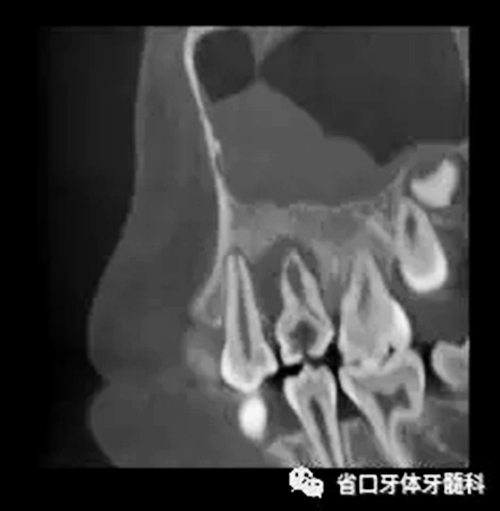

圖3 CBCT(2016-11-13):15由髓腔至根管內(nèi)見團(tuán)塊阻射影像,阻射影中央為透射影,根尖1/3處見根管膨大,腭側(cè)牙槽骨破壞,根尖周低密度影范圍大,上頜竇黏膜增厚。

牙內(nèi)陷并發(fā)牙髓炎、根尖炎時(shí),由于其根管結(jié)構(gòu)復(fù)雜,以往的 X 線根尖片或曲面體層攝片難以全面地顯示根管內(nèi)的腔隙形態(tài),導(dǎo)致臨床治療困難,預(yù)后較差[8]。本病例聯(lián)合使用CBCT、顯微鏡及熱牙膠技術(shù),使診斷和治療過程更加精準(zhǔn),從而保證了治療效果。